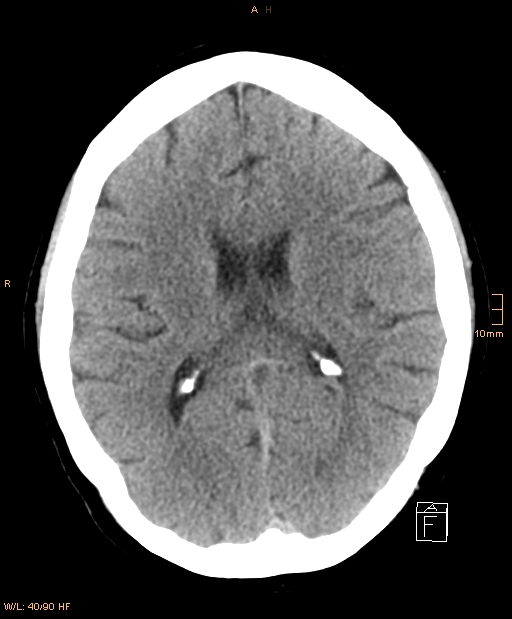

Schädel-CT Normalbefund mit Verkalkungen des Plexus choroideus in den Seitenventrikelhinterhörnern